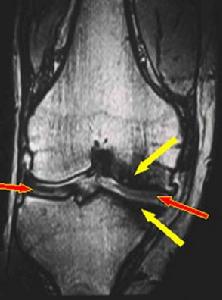

5.關節病變:多關節炎是本病的第2個常見的初發病症,典型的表現為遊走性、非對稱性、非變形性關節炎,可累及周圍或中軸的大小關節。呼吸道軟骨炎可引致鼻軟骨萎縮塌陷,表現為鞍鼻畸形。喉、氣管及支氣管受累可引致嘶啞、氣梗、甲狀腺軟骨上觸痛咳嗽、喘鳴或喘息。主氣道的萎縮塌陷,常引致呼吸阻塞,並有很高的病死率,需要緊急診斷與處理。嚴重氣道受累的患者,常繼發上下呼吸道感染。發生率70%,可為一過性單發不對稱的大關節病變,也可為持續的多發性對稱性小關節病變。最常累及的關節為掌指關節、近端指間關節和膝關節,其次為踝關節、腕關節、肘關節。也可累及胸骨旁的關節,如肋軟骨、胸骨柄及胸鎖關節等。骶髂關節及恥骨聯合在RP中也可累及關節炎常為突然發作非破壞性及非畸形性,出現局部的疼痛和壓痛,可伴腫脹病變發作數天至數周后自行緩解或抗炎治療後好轉關節的累及與疾病的活動無關。RP病人也可伴有破壞性關節病變疾病,如成人銀屑病關節炎、幼年類風濕關節炎、賴特綜合徵、乾燥綜合徵、強直性脊柱炎等。

5.氣管支氣管瀰漫性狹窄變形應與感染性肉芽腫病、硬結病、氣管的外壓性狹窄、結節病腫瘤、慢性阻塞性肺疾病的劍鞘樣支氣管病、澱粉樣變、先天性氣管和支氣管軟化症等疾病鑑別,一般上述疾病經活組織檢查可明確診斷(圖9,10,11,12)。

8.RP關節病變多種多樣,以多個外周小關節受累的要與類風濕關節炎鑑別;以單個大關節受累的要與關節細菌感染、反應性關節炎等鑑別;以一過性遊走性關節疼痛為主要表現的有時會被認為是偽病。RP臨床上可與結締組織病合併存在,使診斷更加複雜。

1.X線檢查:胸片顯示有肺不張及肺炎。氣管支氣管體層攝影可見氣管、支氣管普遍性狹窄,尤其兩臂後伸挺胸側位相可顯示氣管局限塌陷。同時也能顯示主動脈弓進行性擴大,升和降主動脈耳廓、鼻、氣管和喉有鈣化。周圍關節的X線顯示關節旁的骨密度降低,偶有關節腔逐漸狹窄但沒有侵蝕性破壞。脊柱一般正常,少數報告有嚴重的脊柱後凸、關節腔狹窄、腰椎和椎間盤有侵蝕及融合改變。恥骨和骶髂關節有部分閉塞及不規則的侵蝕。